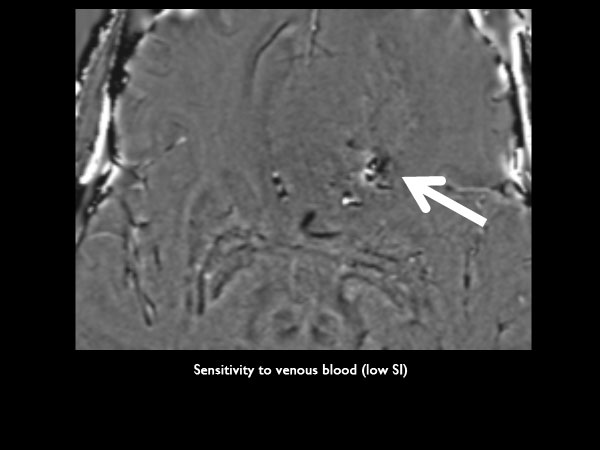

Standard SWI

Axial SWIp (phase)